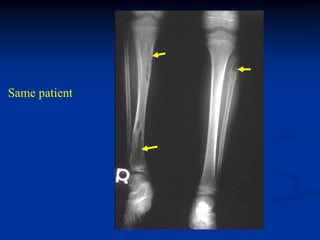

Case #574

2 year male

Ollier’s lower

extremity